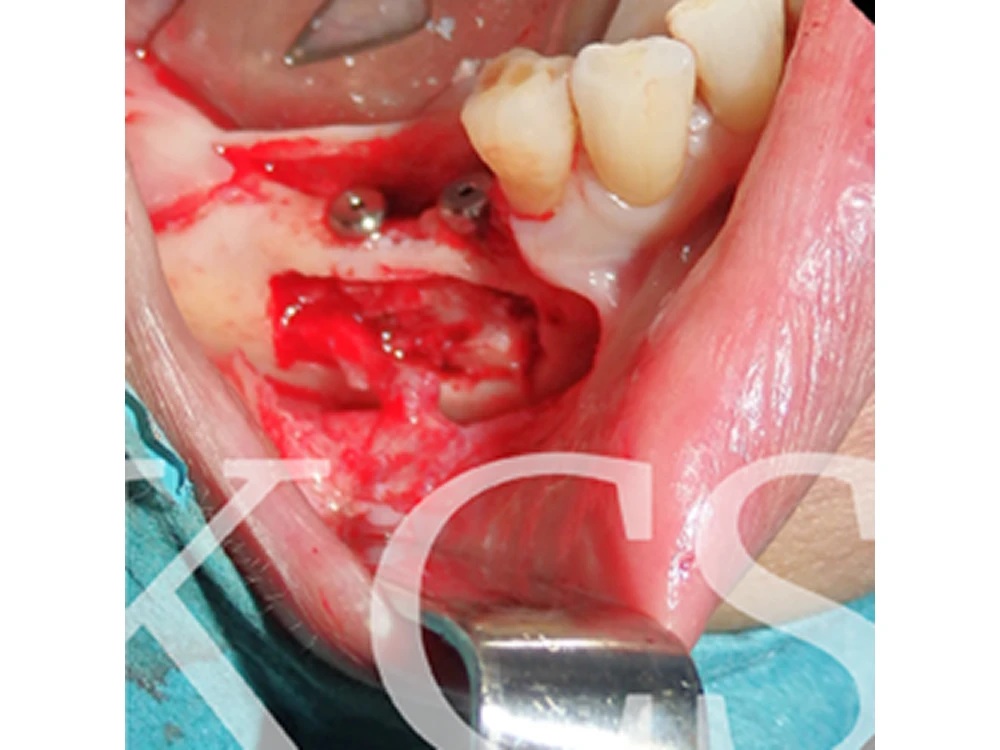

För att ha möjlighet att utföra implantatbehandling så kan vi ibland behöva skapa mer ben. I vissa fall kan det saknas ben vilket behövs för behandling, vi kan då skapa mer ben genom att gå in i bihålan.

Patientfall tandimplantat malmo tandimplantat Malmö

Bild från operation med öppning in till bihålan och anläggning av benersättning. I detta fall placerades tandimplantat samtidigt.